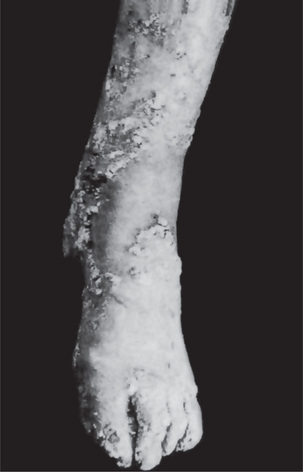

Keratosis follicularis is usually manifested during childhood or adolescence and has an equal gender distribution. The cutaneous lesions appear as small, firm papules, which are red when they first appear, but characteristically become grayish brown or even purple, ulcerate and crust over (Fig. 19-14). Especially in the skin folds, the lesions tend to coalesce and produce verrucous or vegetating macerated, foul-smelling masses. They are generally distributed on the forehead, scalp, neck and over the shoulders, but often spread to the limbs, chest and genitalia. Palmar and plantar keratotic thickening may be so severe as to interfere with function. In severe cases, all the intertriginous areas are involved. Characteristic nail changes are also seen consisting of splintering, fissuring, longitudinal streaking and subungual keratosis.

The oral lesions appear as minute, whitish papules which feel rough upon palpation. Some cases have been described as rough, pebbly areas with verrucous white plaques or as having a cobblestone appearance as in the cases of Weather and his associates and Prindiville and Stern. These are most frequently found on the gingiva, tongue, hard and soft palates, buccal mucosa and even the pharynx (Fig. 19-15).